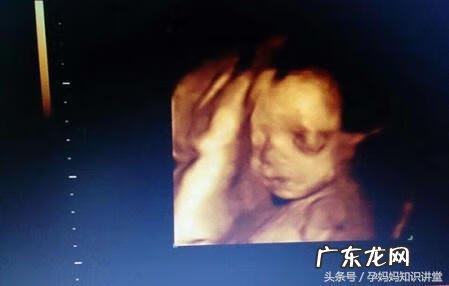

文章插图